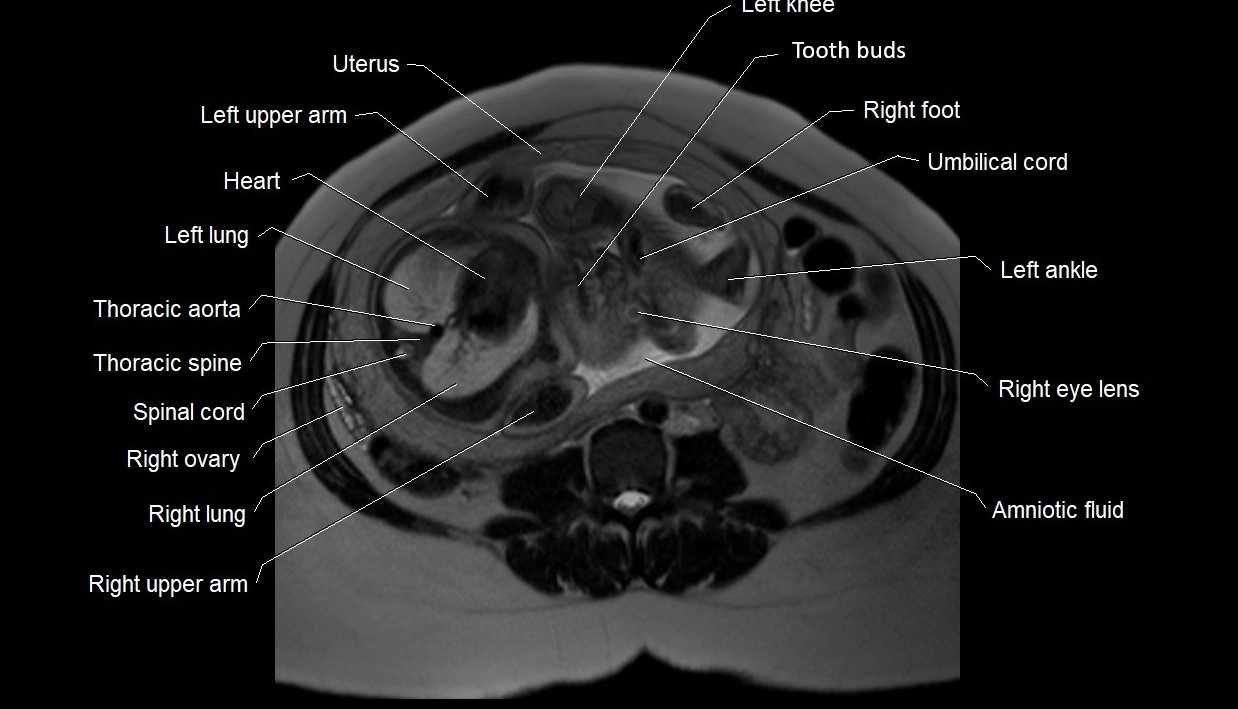

MRI Appearance

T2 HASTE (T2 GRE):

• Amniotic fluid shows very bright hyperintense signal

• Provides natural contrast against fetus and placenta

• Small particles (vernix) may appear as scattered hypointense foci within bright fluid

MRI image

image